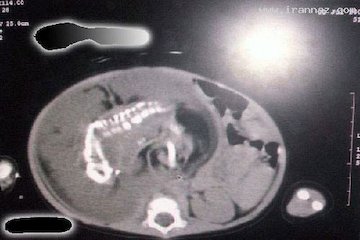

رشد جنین در داخل جنین دیگر ممکن است یک بار در پانصد هزار حاملگی روی دهد. و این پدیده همواره در مراحل اولیه بارداری رخ می دهد. به عنوان یک اصل، معمولا جنین دوم در رحم مادر خواهد مرد و به شکل فعلی حاملگی روی نخواهد داد. اما اگر جنین دوم نمیرد به عنوان یک انگل در بدن جنین اول باقی خواهد ماند و از سیستم گردش خون کودک تغذیه خواهد کرد.

بنابراین، زندگی جنین دوم ذاتا مانند یک تومور مهاجم در بدن جنین اول است. و به جای یک جنین کامل به شکل یک تراتوم به خصوص به خوبی تمایز نیافته خواهد بود و در بدترین حالت به شکل teratocarcinoma (تراتوکارسینوما) خواهد بود که متاستاز نیز می دهد. از نظر بلوغ جسمی ارگان های آن برای تامین خون از بدن میزبان استفاده می کنند، و موجب اختلال در عملکرد ارگانهایی مانند مغز، قلب، ریه، دستگاه گوارش، دستگاه ادراری کودک اصلی می گردند. نمونه دیگر از حاملگی در کودکان که تاکنون اعلام شده عبارت است از :

• در ماه اوت سال ۲۰۰۷، کودک ۲ ساله در فیلیپین به نام Eljie Millapes با جنین در داخل شکم تشخیص داده می شود. پدر و مادر او از رشد غیر طبیعی معده کودک خود از دو ماه قبل از آن نگران بودند. پزشکان بعد از بررسی کشف نمودند که او از داشتن یک جنین در شکم خود رنج می برد.

• در ماه ژانویه سال ۲۰۰۸، کودک ۲ ساله در شهر Medan، اندونزی به نام Afiah Syafina با تومور در معده اش تشخیص داده میشود. پس از عمل جراحی پزشکان شگفت زده شدند زیرا تومور بسیار به جنین پنج ماهه شباهت داشت.

• در ماه مه سال ۲۰۰۸، یک جنین دو اینچی از شکم یک دختر نه ساله در بیمارستان عمومی لاریسا شهر آتن خارج شد این جنین که به شکل تومور بود دارای سر، مو و چشم بود، اما اثری از مغز و بند ناف در آن وجود نداشت.